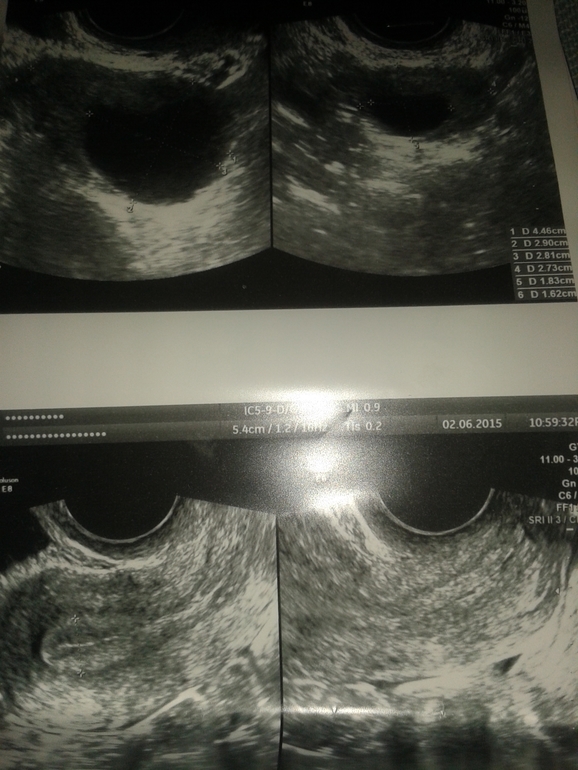

ФолликулометрияДелала тесты на овуляцию за 3 дня до узи и они были положительные.Старались в эти дни.Пошла на узи с увереностью что овуля была.А они кисту нашли.И почему то мучают меня сомнения.1) узистка не уверена была и диагноз под вопросом.2) по размеру она 29 мм (насколько я знаю кистой счетается от 30 мм)3) бт 36, 9 поднялась 4) у меня все гормоны впорядке я сдавала недавно 5) у меня некогда кист не было.Вопрос вот в чем могла ли она ошибится? Просто так надеелись на беременность :( Может у вас были какие то случаи похожие и чем все закончилось?

Такое часто бывает!Фактически кистой называют образование от 30 мм, все верно. С другой стороны дать , что фолликул будет больше 25 мм тоже странно. Обычно при таких размерах фолликул уже овулирует. возможен еще и третий вариант- кровоизлияние в желтое тело, образование кисты желтого тела. Это не мешает вам беременеть.

М -эхо шикарное! По фолликулярной кисте непонятно... правда на нее похоже... сделайте еще узи через 3 дня. Возможно не хватидо ему уровня ЛГ для того чтобы лопнуть!

Ддя фолликула размер очень большой! Надо делать узи с допплером... чтобы смотреть есть ли кровоток в этом образовании, потому что это может юыть ЖТ наполненное кровью после разрыва сосуда когда овулировал фолликул!